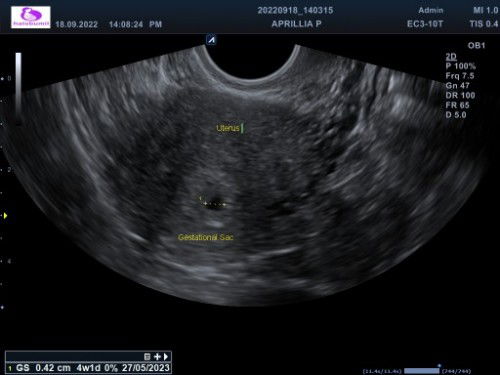

Bunda bunda kan aku terakhir haid 31 juli nah pas 31 agustus aku kan ke dokter ternyata pas diusg gaada apa apa dirahim ku bersih juga, trs dikasih obat perangsang biar haid klo sampe tgl 17 sep ga haid tgl 19 sep disuruh kontrol lg buat di cek lg tp klo haid gausah balik lg katanya, nah kmrn terakhir tespek 3 sep masih negatif, pas tadi pagi tespek garis 2 samar, niatnya nanti kamis & minggu aku mau tespek lg, menurut bunda bunda aku balik lg ke rs ga ya tgl 19? Klo balik lg ngomongnya gmna ke dokternya ya bingung hehe #seriusnanya #bantusharing #pleasehelp #firstbaby